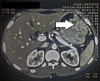

Presentation of case: Female patient 35 years old complaining of severe epigastric pain, dyspepsia, nausea and vomiting for 1 year. Upper GIT endoscopy and CT scan revealed thickening of gastric mucosa. Endoscopic biopsy was non-specific but showed moderate grade dysplasia and no Helicobacter pylori infection. All laboratory investigations were within normal including serum albumin. She underwent total gastrectomy with marked postoperative improvement of symptoms after recovery. Postoperative pathology revealed gastric fovular hyperplasia and glandular atrophy which are diagnostic for Menetrier's disease.